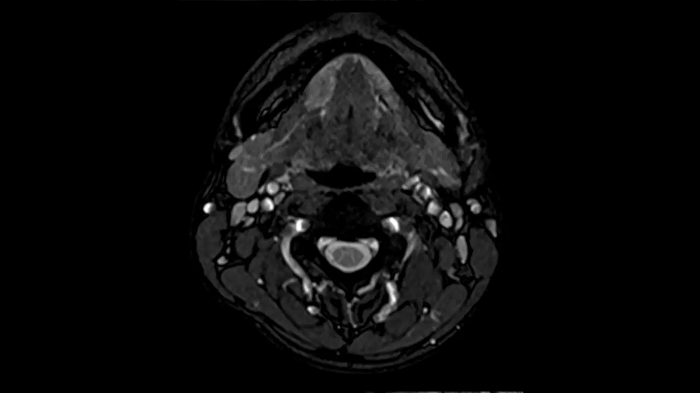

Neck

Excellent soft tissue contrast in the neck

An all-inclusive soft tissue investigation in the head with outstanding image quality for T1, T2, and diffusion contrast.

MAC-ID: 7aaaa0158. Image Credit: Siemens Healthineers